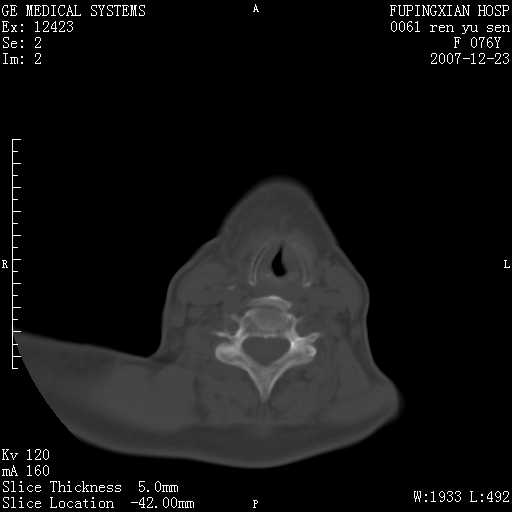

男性 76岁 下颌右侧磨牙区肿物数月, 约2.0*1.5cm大小波及颊舌侧,伴颌下淋巴结肿大。余(-)

右颈部颌下腺前可见一类圆形软组织密度影,密度不均,内见小片坏死区.颌下颈前可见两枚肿大淋巴结影.考虑淋巴结感染可能性大,建议增强扫描..

右侧第四磨牙缺失,局部牙槽骨质破坏,边界欠清晰,同侧颌下及竟不见多发肿大淋巴结显示。考虑肿瘤病变可能性大,感染待排